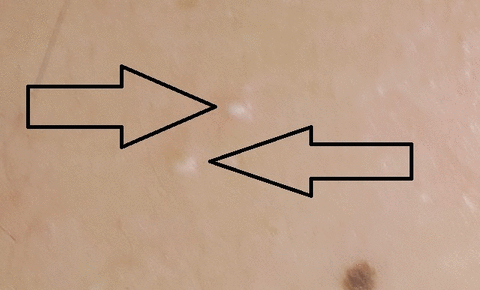

この症例では、患者さんの右ホホに二つ出来ていました。

拡大です。